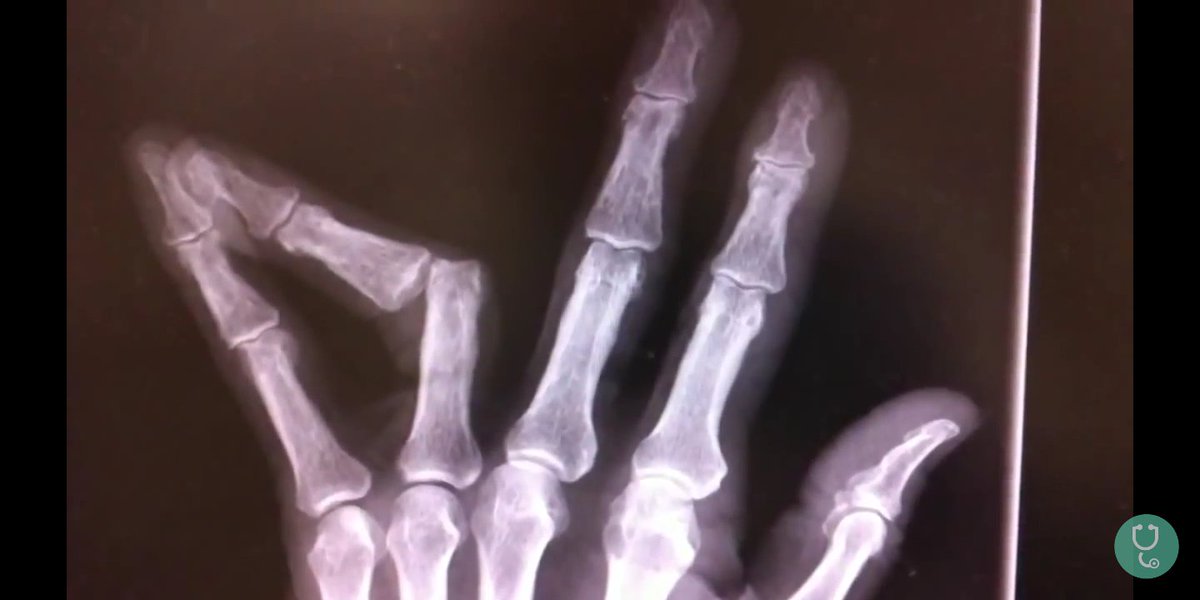

Указательный палец выбит

Указательный палец выбит 117 фотографий